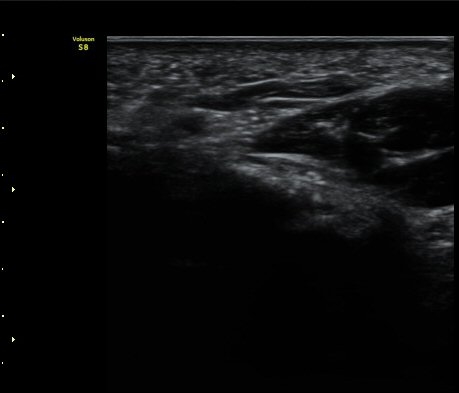

ŽÃËÀÚ¸¦ Á» ´õ ³»ÃøÀ¸·Î °æ»ç¸¦ ÁÖ¾î °¥°í¸®»À °í¸®ÀÇ Ãø¸éºÎ¸¦ °üÂûÇÏ´Ï °¥°í¸®»À °í¸®ÀÇ

ÇÇÁú°ñ ¿¬°á¼º ¼Ò½Ç(°ñÀý)°ú ±¹¼ÒÀû Àú¿¡ÄÚ ºÎÁ¾ÀÌ °üÂûµÇ°í Àú¿¡ÄÚ ºÎÁ¾ ¿ÜÃø¿¡¼­ ö°ñ½Å°æ

½ÉºÎ°¡Áö°¡ °üÂûµÈ´Ù(±×¸² 2, 3, 4,).